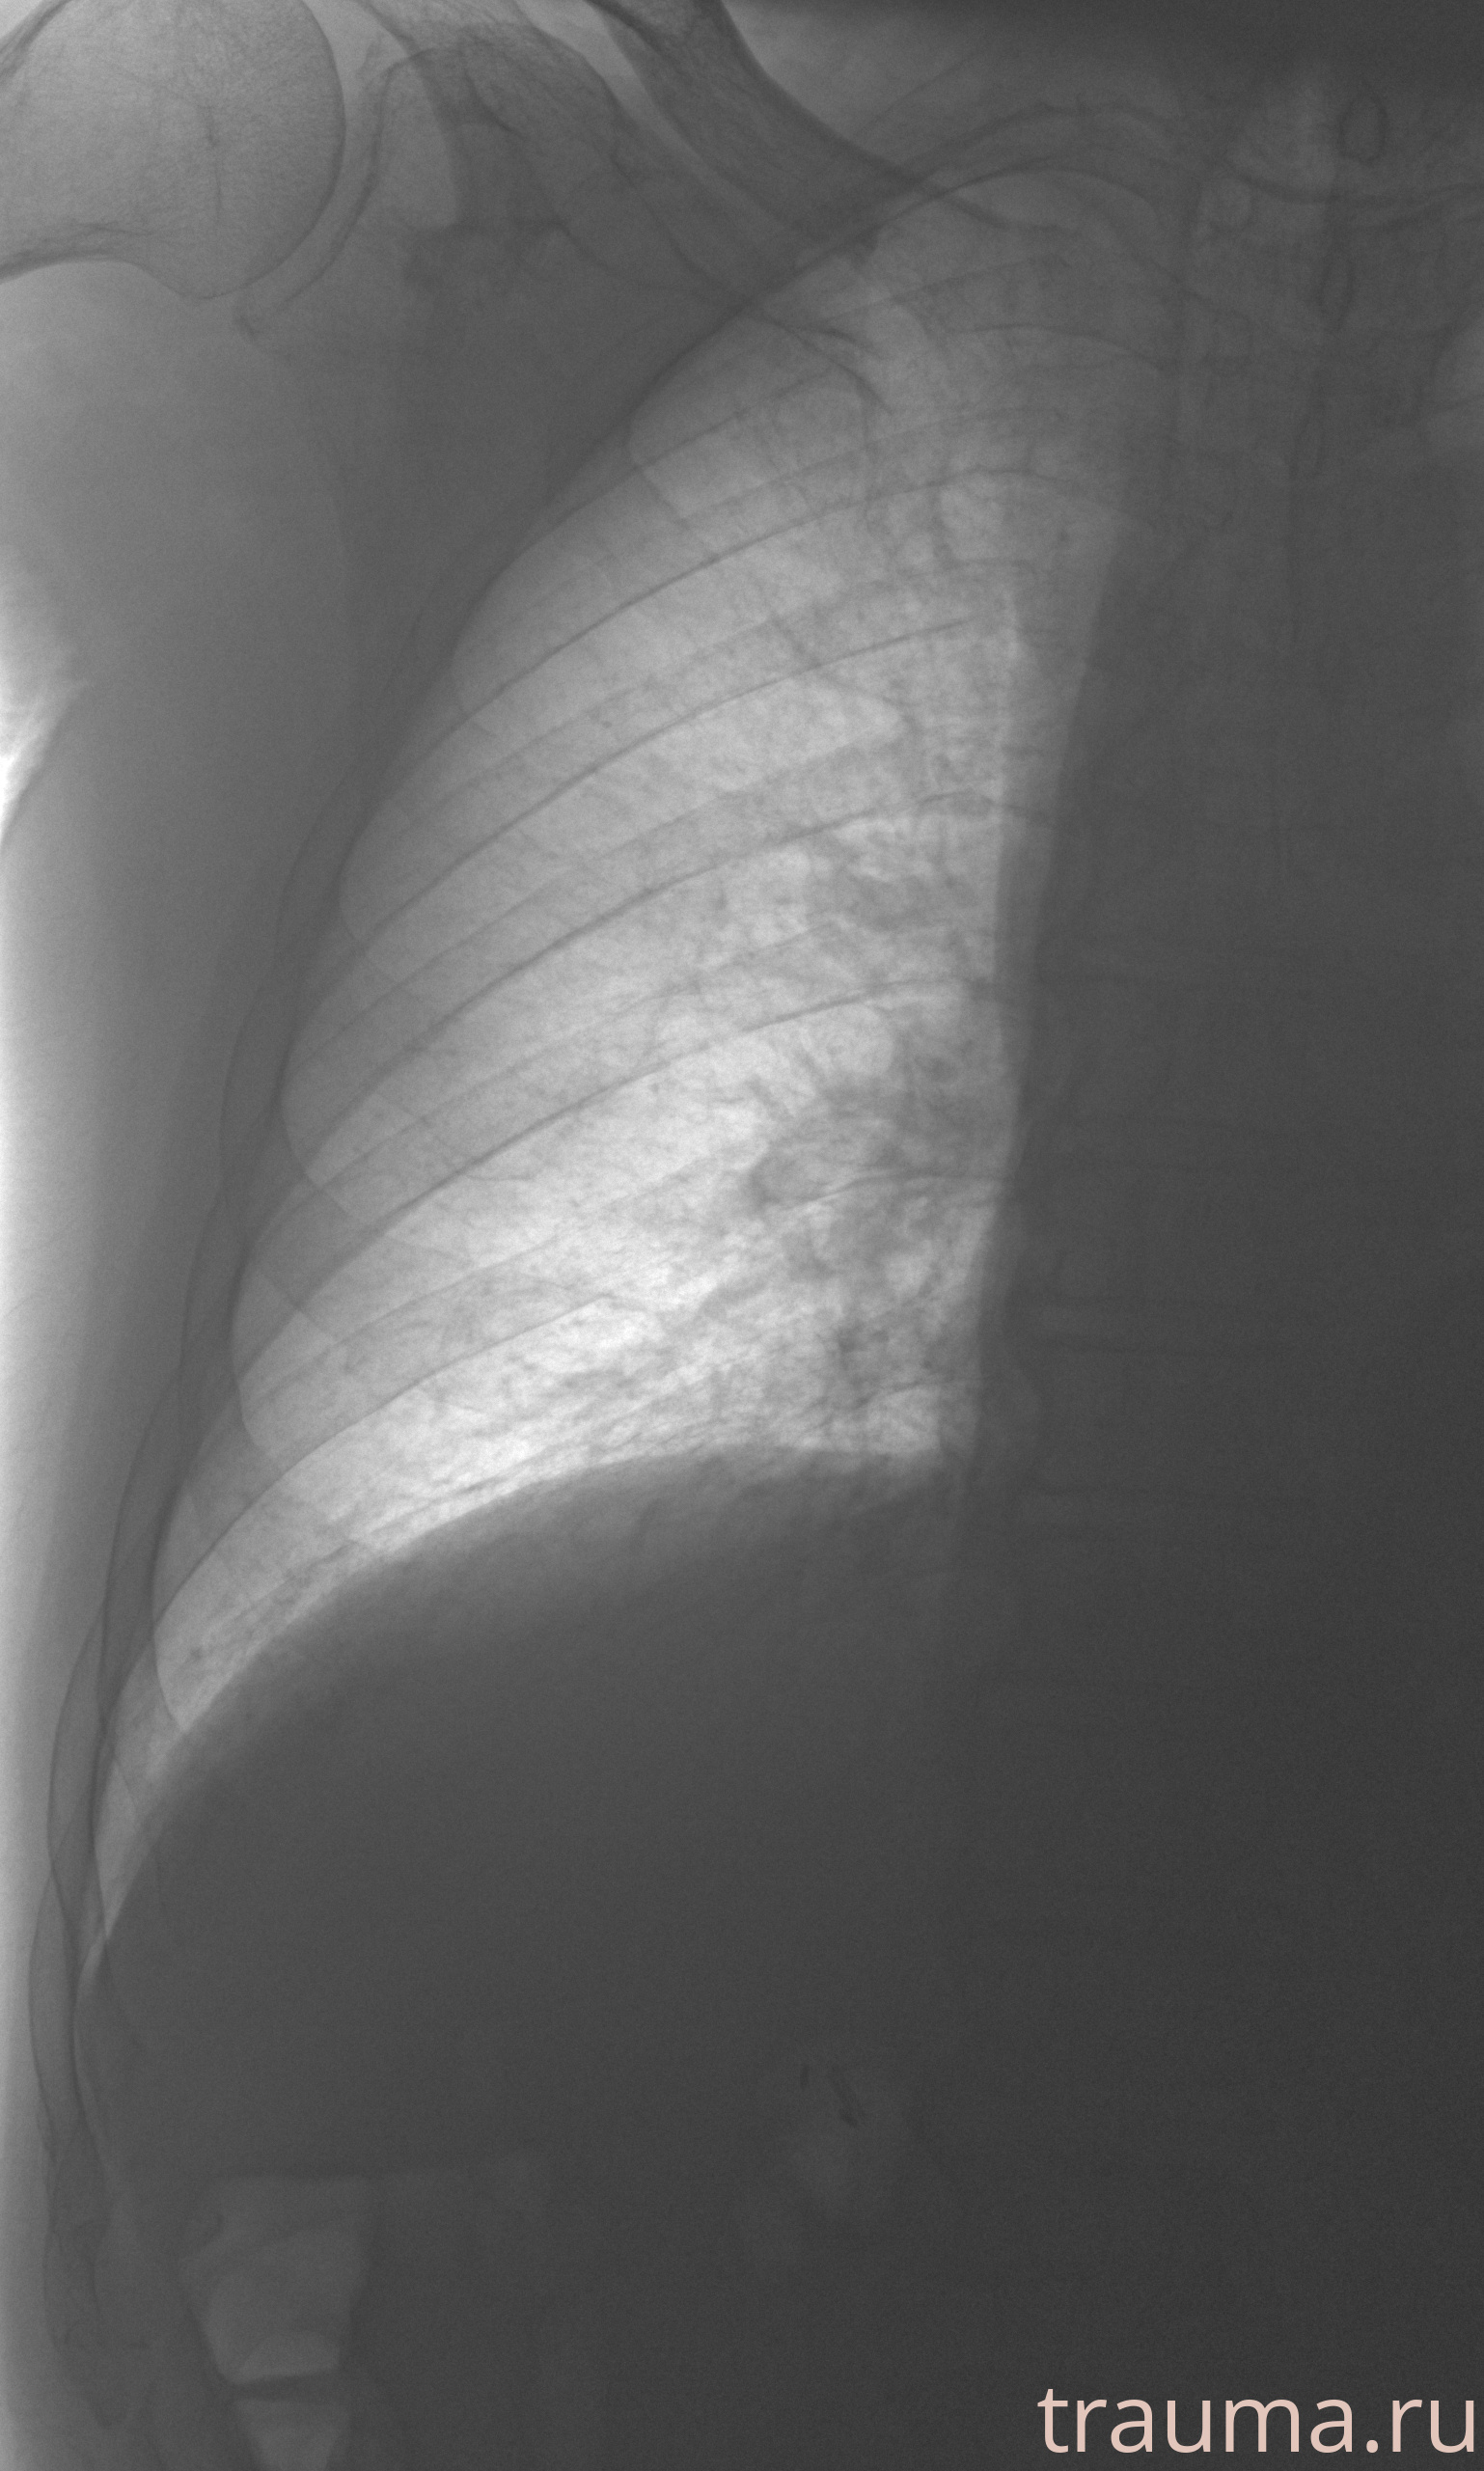

Рентген на дому: по вашему адресу приезжает врач-рентгенолог, травматолог-ортопед с мобильным рентгеновским аппаратом, проводит диагностику травмы или заболевания, делает необходимые рентгенограммы, дает рекомендации по дальнейшему лечению. Получить качественные снимки в домашних условиях возможно благодаря уникальной методике, разработанной МосРентген Центром для института  Склифосовского